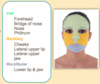

What are the 4 components of the face embryologically?

- Frontonasal prominence (FNP)

- Stomatodeum (buccopharyngeal membrane)

- 1st Pharyngeal arch which can be divided into:

- Maxillary prominence

- Mandibular prominence

What do each of the components of the face become i.e. what are their derivatives?

What are the fates of the facial prominences?

- FNP: forehead, bridge of nose, medial and lateral nasal prominences

- Medial nasal: philtrum, primary palate, mid upper jaw

- Lateral nasal: sides of the nose

- Maxillary: cheeks, lateral upper lip, secondary palate, lateral upper jaw

- Mandibular: lower jaw and lip